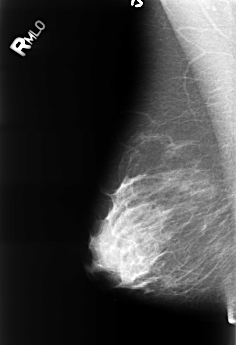

B_3243_1.RIGHT_MLO

RIGHT_CC LINES 4528 PIXELS_PER_LINE 3080 BITS_PER_PIXEL 12 RESOLUTION 50 NON_OVERLAY

RIGHT_MLO LINES 4480 PIXELS_PER_LINE 3064 BITS_PER_PIXEL 12 RESOLUTION 50 NON_OVERLAY